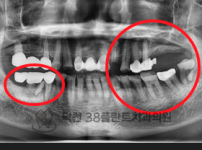

치료전후